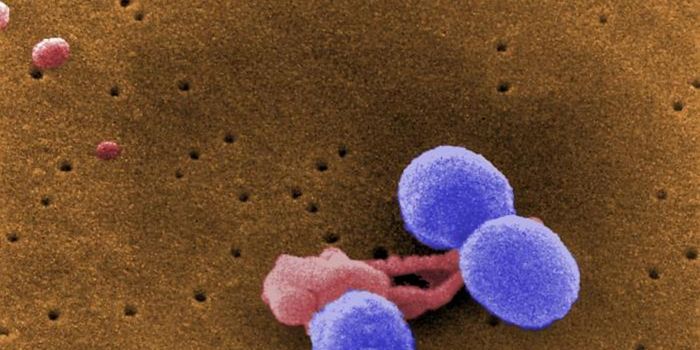

MAR 18, 2016ImmunologyHow are macrophage immune cells activated during an inflammatory response when pathogens invade? Scientists thought they ...